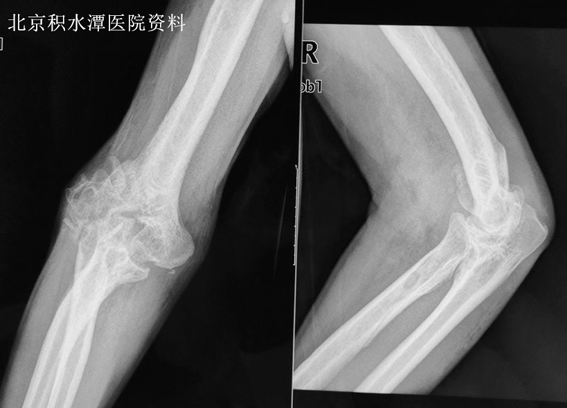

术前见关节面严重破坏

老张是位京郊农民,由于车祸导致肩胛骨骨折和肱骨髁间开放性粉碎骨折。当地医院为他进行了肩胛骨内固定手术,但因为肘部软组织损伤较重,未对肱骨髁间骨折进行治疗。9个月后,老张的肱骨远端破坏严重、畸形愈合,仅有10度的轻微活动度,疼痛更加明显。多个医院就诊后,医生都建议他到北京积水潭医院行全肘关节置换。

由于老张的肱骨远端关节面严重破坏粘连,团队首先为他进行彻底的关节松解,将关节脱位后,见肱骨远端关节面骨质增生明显,畸形愈合。通过模板截骨后,在肱骨远端假体中植入松质骨,安装假体,打压固定,并通过侧方两枚螺钉稳定假体。修整尺桡骨近端关节面,复位关节后,见肱尺和肱桡关节对合良好。术中检查活动度良好。冲洗止血,内外上髁打孔修复内外侧副韧带和肌腱止点后,检查关节稳定。术后石膏制动三周以保护侧方软组织稳定性。